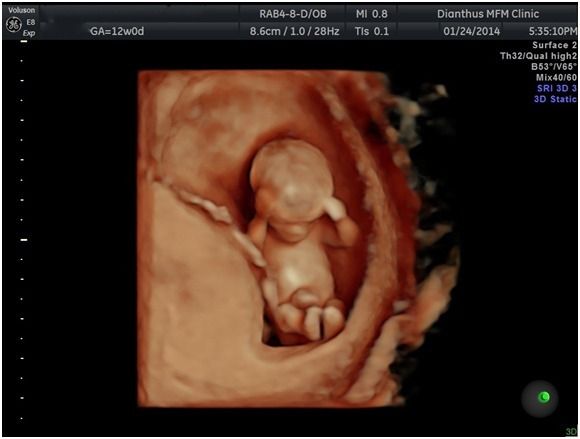

至於進一步來談談3D/4D超音波,3D超音波就是立體超音波,利用影像資料重組出寶寶的外觀,就和照相一樣,而4D超音波則是再加上動態的錄影,一般的3D/4D並不具診斷的功能,而是一種讓準爸媽提早與寶寶見面的立體動態影像工具。

所以,有醫師會說,傳統二維超音波就足夠做診斷的用途了,3D/4D只有娛樂價值、噱頭啦。其實沒什麼好爭辯的,基本上,我對於要不要做也沒什麼特別看法。只是,我本就是大嘴巴,所以還是多嘴補充一下,能做3D/4D 的超音波,一定都是高階等級儀器,因為畢竟要重組影像一定要有優良的二維影像解析能力,所以如果大家搞不清楚醫療院所超音波儀器之好壞,這就是一個最簡單的判斷方式了。畢竟二維影像的解析度,就大大關係著診斷之品質嘍。(嗯,我會不會透露太多了,呵呵。)